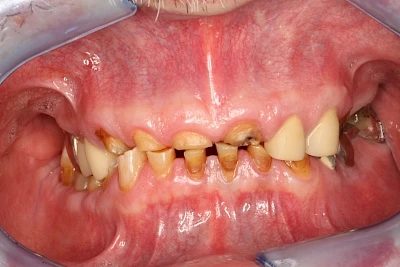

Über die Zeit können verschiedene Prozesse die Zahnhartsubstanzen aufzehren:

- Abnutzung durch Kauen (Abrasion) oder duch durch übermäßiges Knirschen bzw. Pressen (Attrition)

- Säurebedingte Auswaschung (Erosion)

- Knirschen bzw. Pressen und ungünstige Putztechnik (Druck): keilförmige Defekte

Die Zähne können dabei auf Reize (warm, kalt, süß, sauer) oder auch beim Zähneputzen empfindlich oder schmerzhaft sein. In allen diesen Fällen ist es sinnvoll, den Zahnarzt zu kontaktieren und das weitere Vorgehen abzustimmen.

Auswaschung (Erosion) dagegen ist eine Verschleißerscheinung der Zähne aufgrund von immer wiederkehrenden Säureangriffen durch die Nahrung, verstärkt zum Beispiel durch den Genuss säurehaltiger Getränke oder Speisen. Auch bei Menschen mit einer Essstörung (z. B. Bulimie) können die Zähne durch die Magensäure ausgewaschen erscheinen.

Eine Sonderform sind sogenannte keilförmige Defekte im Bereich der Zahnhälse. Hier geht man davon aus, dass Knirschen und Pressen in Kombination mit falschen Putzgewohnheiten (zu hoher Putzdruck, Verwendung von Zahnpasta mit hohen Abrasionswerten) eine Rolle spielen.